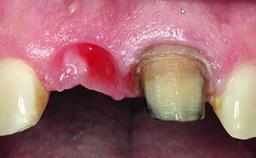

Replacement of a Failing Upper Left Central Incisor: Immediate Placement of an RC Bone Level Implant and Provisionalization

A healthy 23-year-old female patient was referred for a consultation on replacing tooth 21 with an implant-supported restoration. The patient had recently moved to the area and reported a history of endodontic and periodontal treatment for tooth 21. The tooth had been deemed non-restorable by her previous periodontist but since she was going to be moving, he recommended consulting to a dentist in her new city to continue her treatment. A review of her medical history yielded no significant findings and no known drug allergies. The analysis of her smile revealed a medium to high symmetrical smile line and a slightly discolored tooth 21.